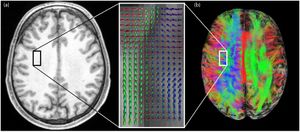

Cluttered fiber tractography visualizations due to the ability to resolve “crossing fibers” at a voxel level and the great overlap of pathways. (a) At the location of the square in the anatomical T1-weighted image (left), the dODFs (visualized as spherical “glyph” representations overlaid on a fractional anisotropy map in the magnified box on the right) reveal fiber crossings at the voxel level [42]. (b) Left hemisphere: pathways greatly overlap, resulting in a cluttered view (superior) in which underlying pathway configurations are hidden. The square indicates the same location as in (a). Right hemisphere: orientation-dependent transparency rendering in which all streamline segments that run in the direction of the viewing axis are rendered transparent. In this way, the underlying structures are revealed and can be explored. |